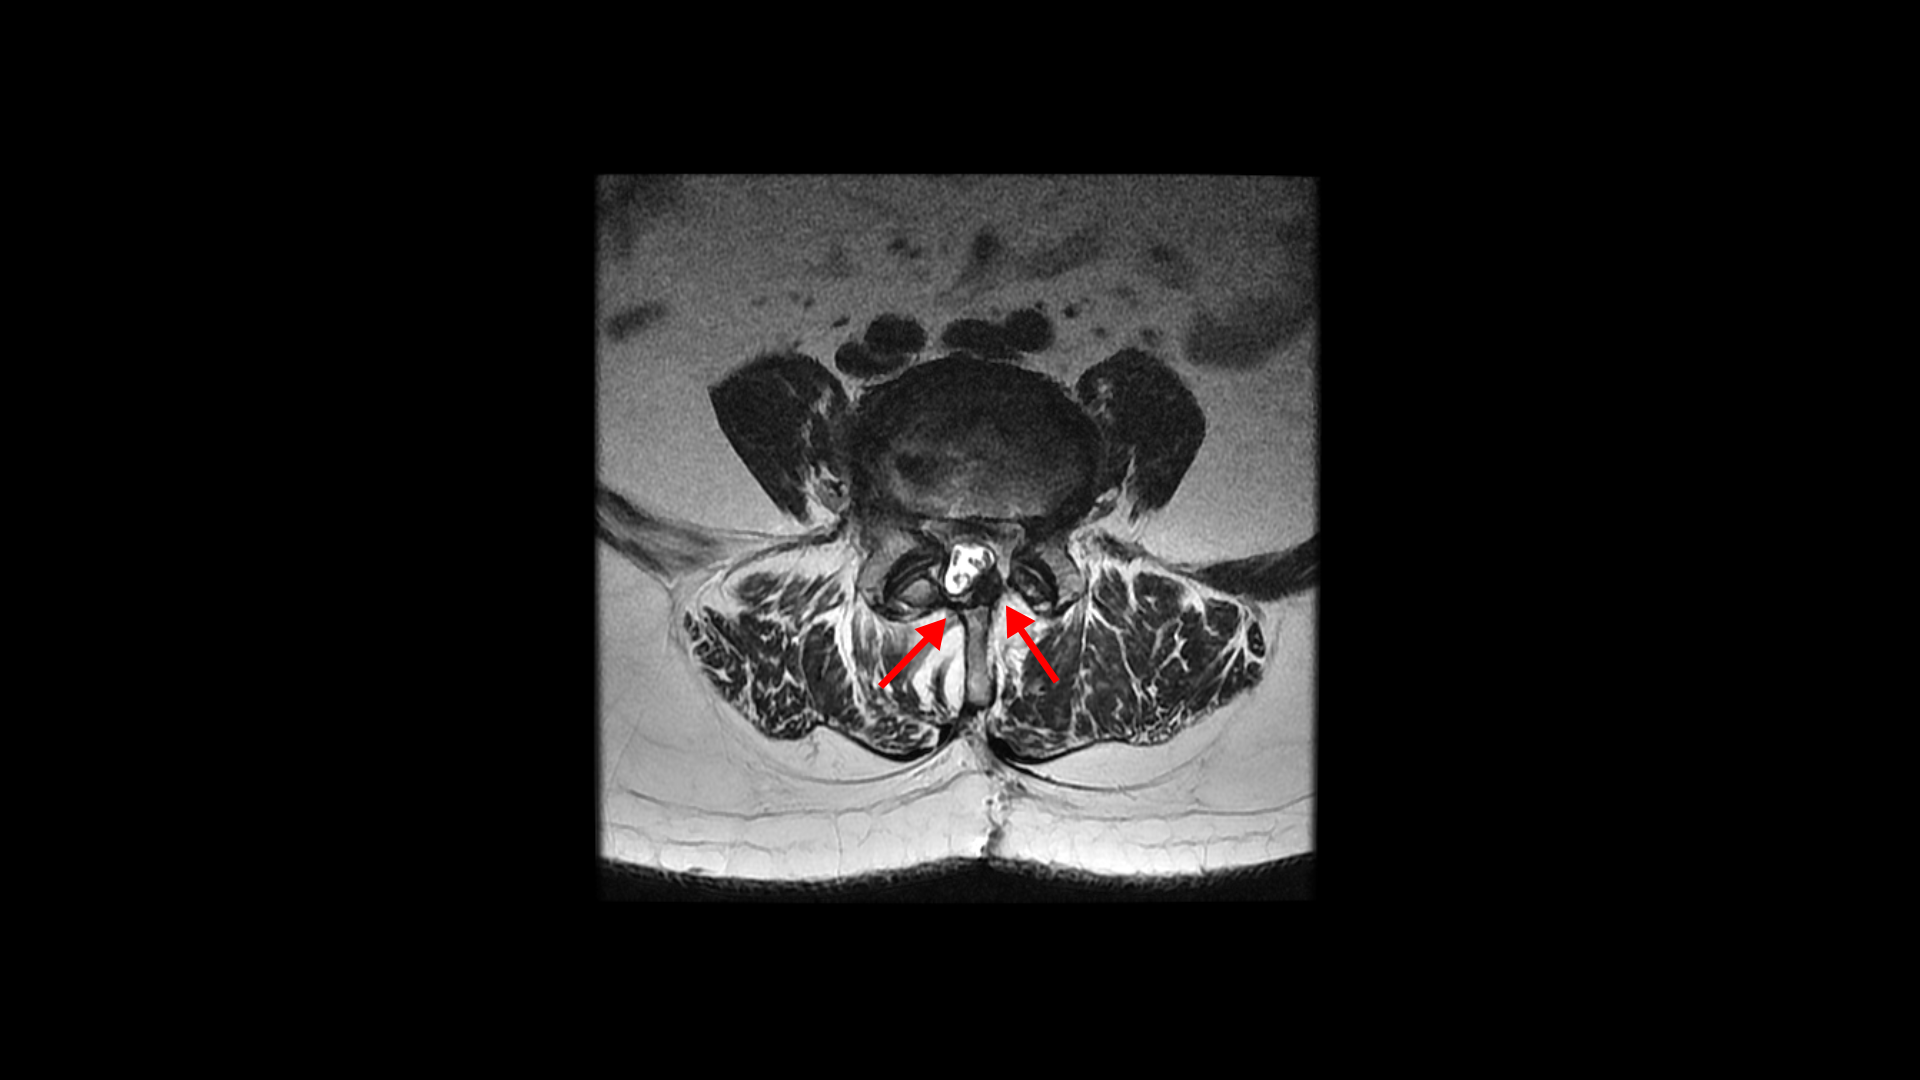

4번 5번 후궁 양쪽으로 수술한 자국이 보입니다.

올해 초에 4번 5번 디스크가 또 오른쪽으로 심하게 파열돼서 결국 후궁과 후관절, 황색인대를 모두 다 제거하고 나사를 박는 척추유합술을 하셨습니다.